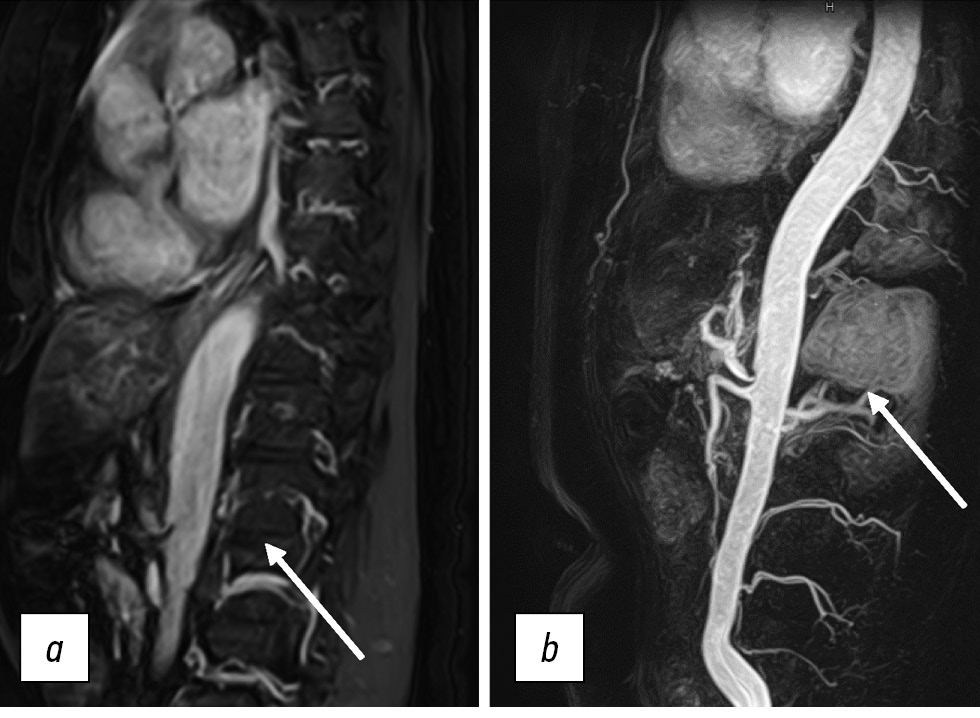

Dynamic pre- and postcontrast T1-WIs can be obtained using 2D or 3D pulse sequences [6], with 3D sequences preferred because minimizing slice thickness reduces truncation artifacts. 3D SGE sequences were initially used to visualize vascular anatomy (MR angiography; Fig. 8). This technique is currently widely used to visualize soft tissue structures in the abdominal cavity and small pelvis. Short repetition time and TE values allow for the acquisition of many thin sections in a single breath-hold. The relatively low SNR of this sequence may be a limitation; however, this disadvantage is offset by the use of intravenous contrast.

Figure 8. Contrast-enhanced magnetic resonance imaging of the abdominal aorta and its branches. Extravascular compression of the celiac trunk by crus diaphragm (arrows): а SSFE; b contrast-enhanced 3D mode.